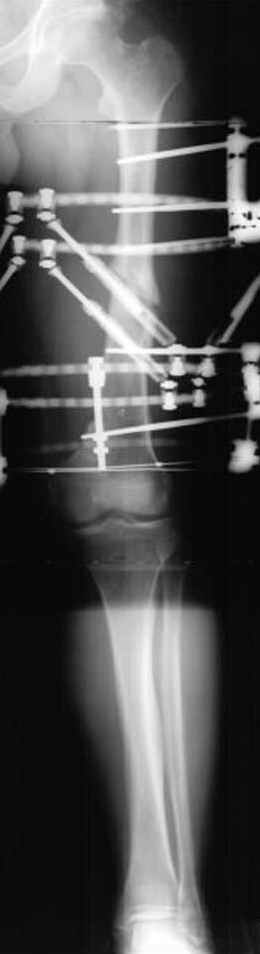

Если, например, доводится лечить больных с псевдартрозами шейки бедра, то надобность есть, и приходится. См. приложение.

пластическая модель; и коррекция бедра аппаратом Илизарова.